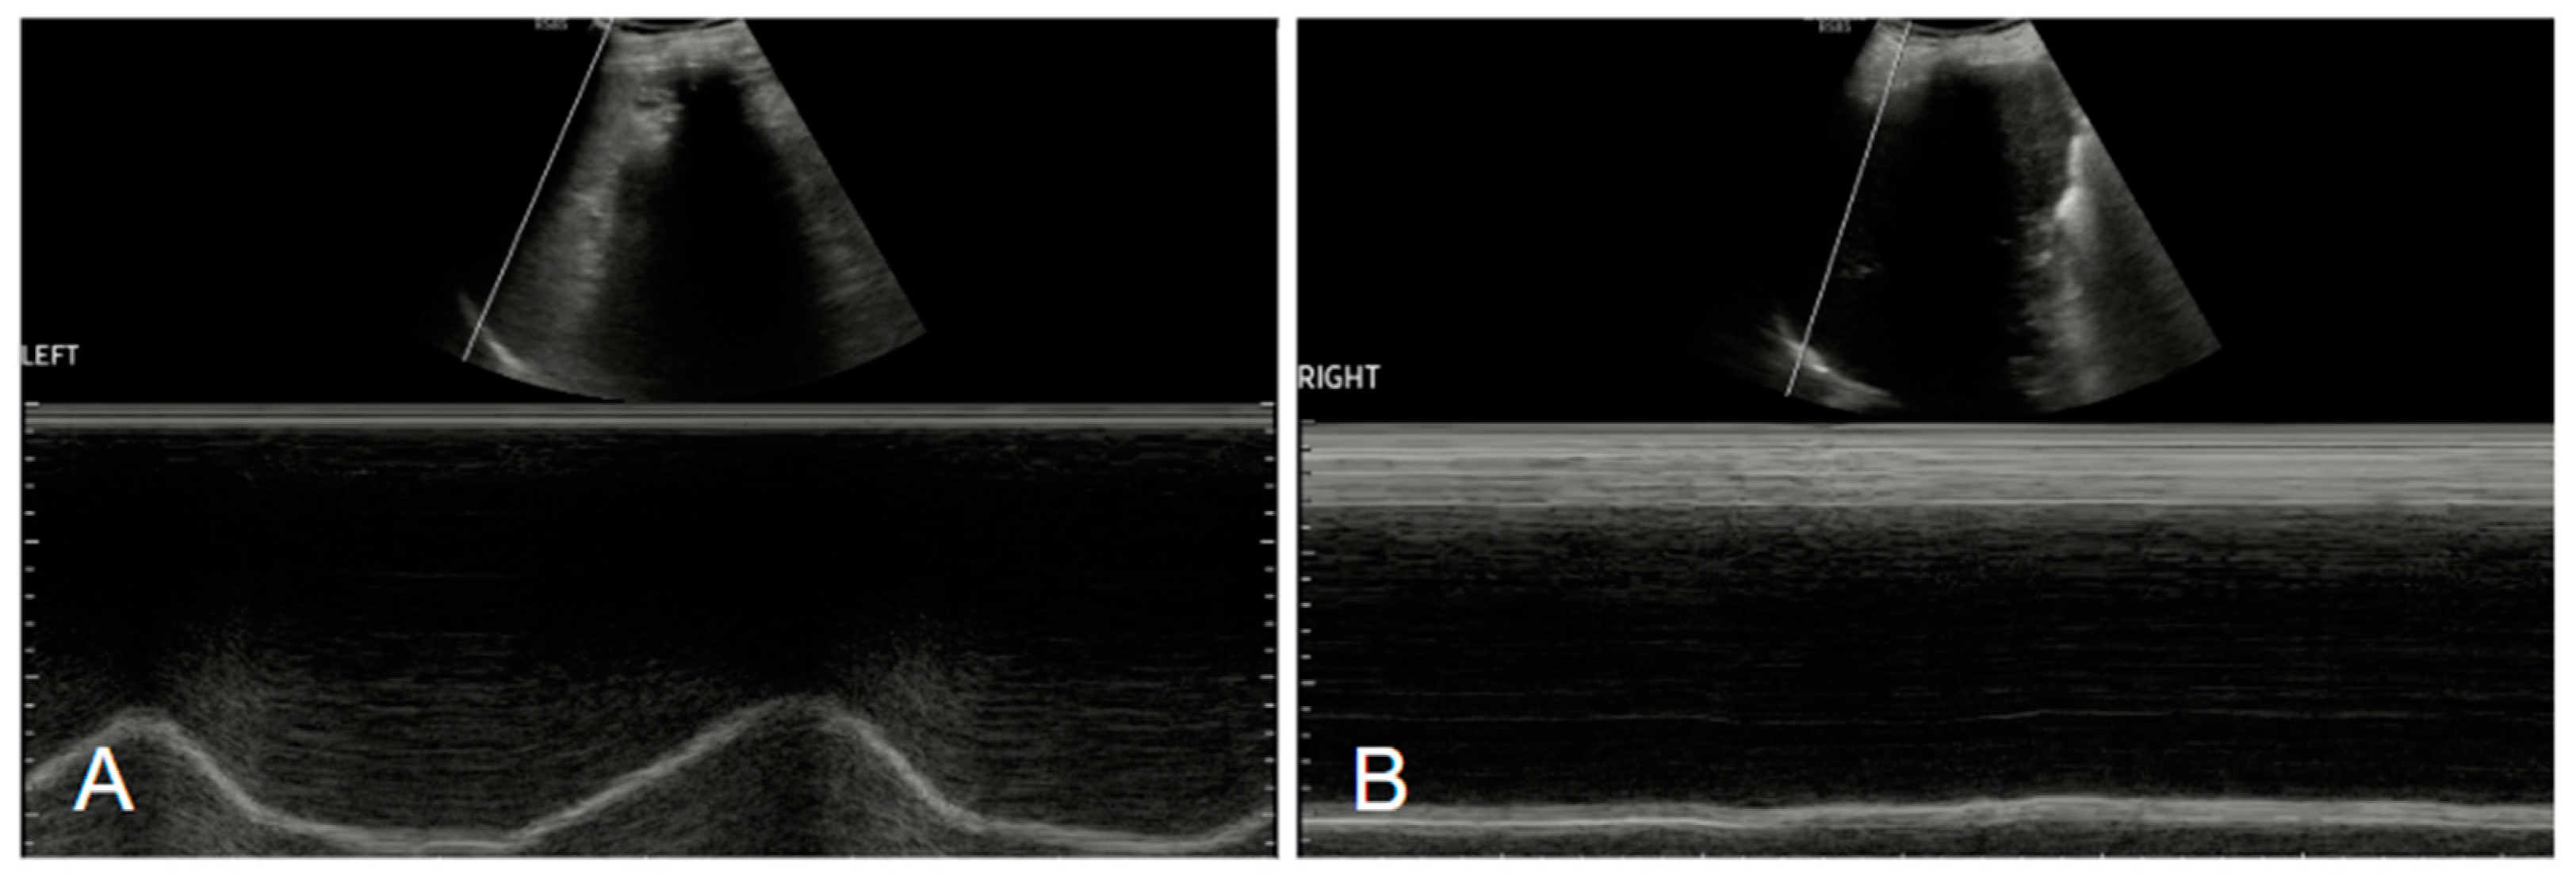

Figure 3.

Ultrasound examinations of our patients. The figure shows M-mode studies of the diaphragm, with normal movement of the left hemidiaphragm (A) and impaired movement of the right hemidiaphragm (B) [6].